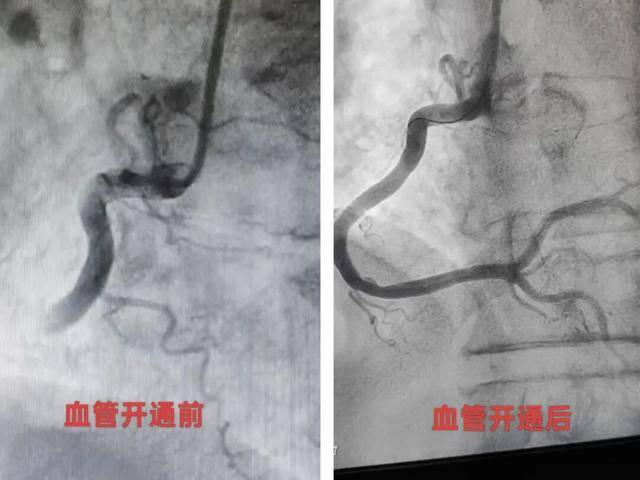

下一步,便是手术。与患者家属充分沟通后,周龙辉与心血管内科二区主治医师廖顶矗紧急为患者行经皮冠状动脉介入治疗(PCI)术,术中冠脉造影显示患者右冠近段堵塞严重。手术团队精准定位,成功找到闭塞的血管,顺利植入支架。术后,患者胸痛症状明显缓解,随后被送至CCU继续监护和治疗。在医护人员精心治疗和护理下,患者恢复良好。